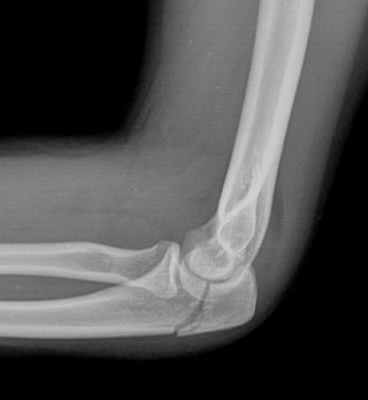

(Слева) На боковой рентгенограмме локтевого сустава визуализируется небольшой отломок перелома кончика локтевого отростка. Края отломка неправильной формы, что отличает это повреждение от несросшегося центра оссификации апофиза.

(Справа) На боковой рентгенограмме у ребенка после падения определяется косой перелом через среднюю точку локтевого отростка с незначительным смещением. Напротив, зона роста локтевого отростка волнистая с выраженным кортикальным слоем по краям. (Слева) На боковой рентгенограмме локтевого сустава после падения на вытянутую руку при согнутом локтевом суставе виден смещенный отломок, оторвавшийся от кончика локтевого отростка. Степень смещения свидетельствует о значительном повреждении трехглавой мышцы.